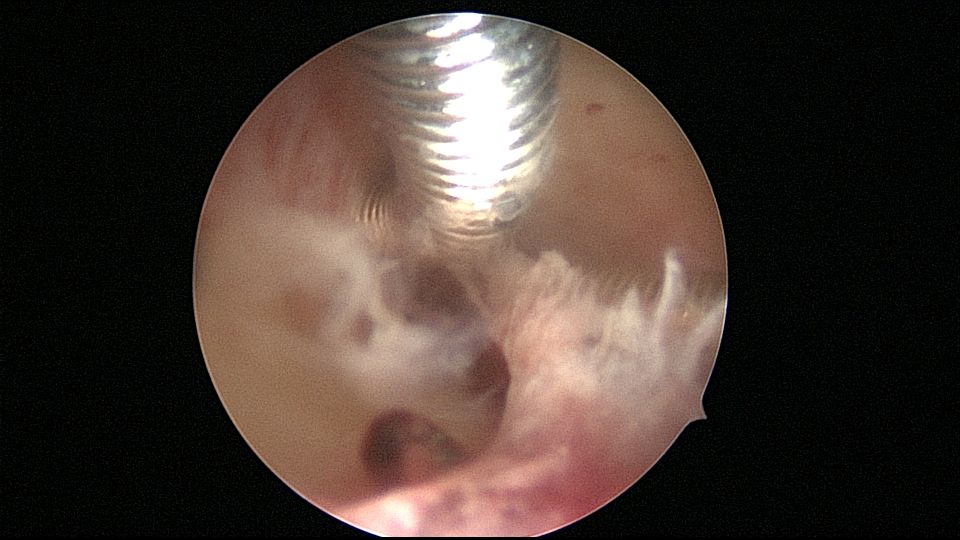

患者56岁,G2P1,顺产1次。安环16年,绝经1年,外院取环失败。宫颈外口及宫颈内口狭小质硬,分别用中弯钳及异物钳扩张,宫腔镜见宫颈管息肉2个,宫型环与宫壁嵌顿,异物钳取出,单级电针切除息肉送病检,病检结果为宫颈管息肉,宫腔未见其他异常。